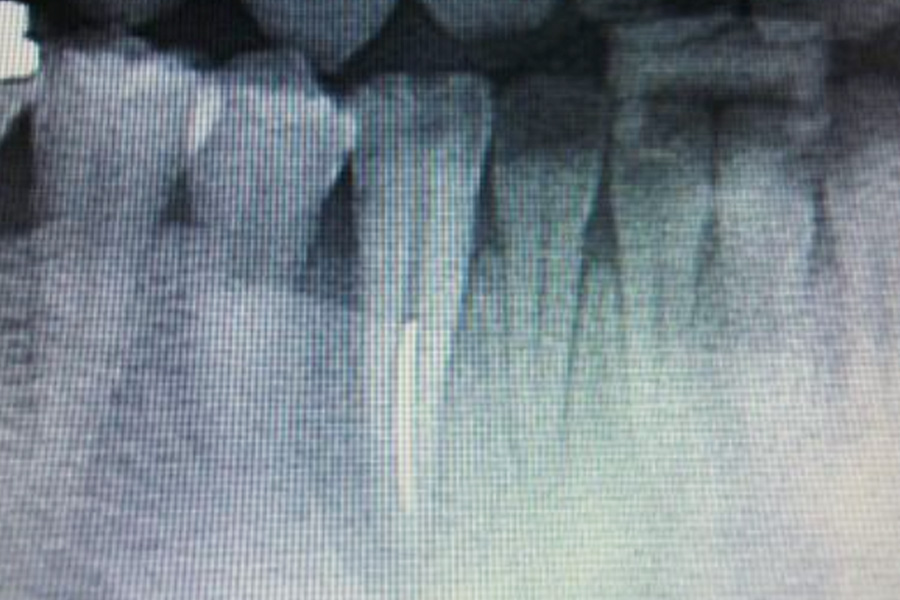

歯周病治療根管治療 根管治療歯周病治療 2026.04.27 噛み合わせと歯周病治療 初診 7ヶ月後 1年後 担当医 山内 先生 主訴 噛み合わせと歯周病治療 期間 1年間 費用 ¥22,000(税込)〜 治療内容 根管治療と歯周外科による保存治療 治療に伴うリスク 治療後も日々の歯磨きや定期検診で清潔な状態をキープする事で 再発を防ぐ事ができる。 関連症例